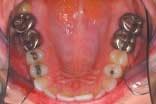

The upper and lower occlusal shots, as well as the four individual quadrants, are captured next. The four individual quadrant shots are the most powerful of the series. These are the shots where a patient can see old restorations, wear facets, recurrent decay, poor contour, etc. It is with the quadrant shot that the patient asks for dentistry. The doctor does not need to sell it!